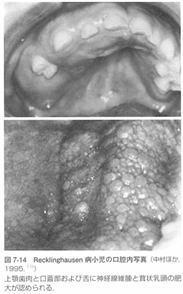

4:レックリングハウゼン病と歯科医療

(1)歯科的特徴

歯肉、舌、口蓋粘膜の神経線維腫。

頭蓋骨や顔面骨の骨欠損があります。

『スペシャルニーズデンティストリー障害者歯科 第2版』から引用